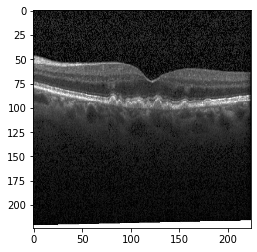

III-B Data Acquisition and Preparation

Optical coherence tomography (OCT) images were selected from retrospective cohorts of adult patients from different hospitals around the world. OCT Images are labeled as (disease)-(randomized patient ID)-(image number by this patient) [11] and Fig 1 shows some examples of OCT images. Image properties are presented in Table II and the distribution of image quantity is presented in Table III. Custom image generators resize images to 224x224x3 and normalize them

Fig 6, 7, 8 and 9 depicts the visualization of correct predictions by our proposed CNN model where fig 6 is class CNV, fig 8 is class DME, fig 7 is DRUSEN and finally, fig 9 is NORMAL. Here the first photo in every class is the original image. The LIME map of our suggested model’s prediction is shown in image B whereas in image C the positive region is highlighted in specific sections on the original image. For Image D we have increased the number of features from 5 to 10 thus more regions have been predicted as the positive region which is highlighted in green. After increasing the features from 5 to 10, some of the regions are predicted wrongly. The red regions represent the output of incorrect prediction. The following image represents the Grad-CAM heatmap highlighting the regions with our model’s prediction.